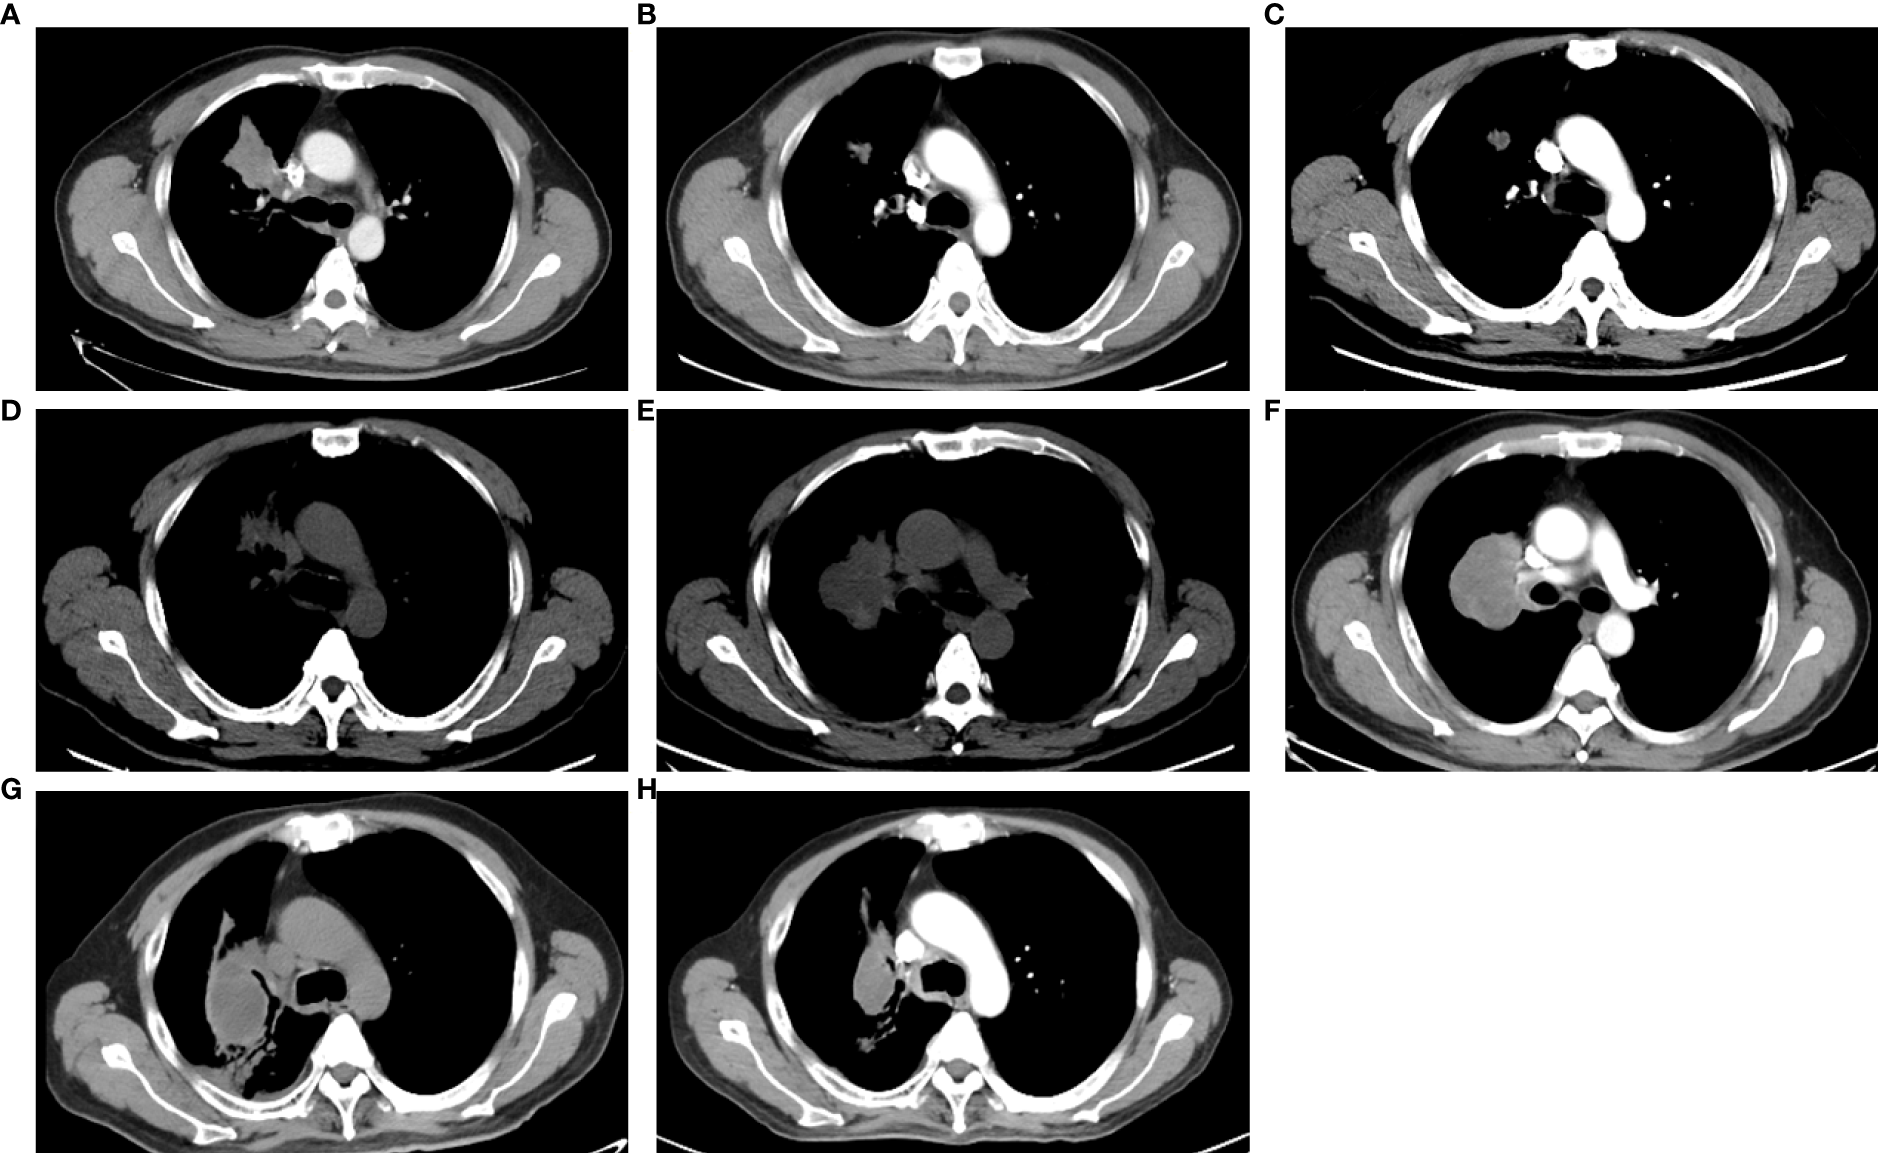

EGFR amplification was validated by fluorescence in situ hybridization (FISH) via tissue biopsies, including pre-treatment biopsies from primary tumors and post-treatment re-biopsies from lung and liver metastasis lesions. FISH signal accounts (copy number) were recorded for a total of 50 nuclei, and the tumor was considered EGFR amplification when EGFR/CEP7 ratio was greater than or equal to 2 in 15% of recorded cells (14). Figure 1A shows that FISH revealed EGFR amplification in the metastatic lesions of both lung and liver, while no EGFR amplification was observed in the primary lesion. Dynamic monitoring of radiological results and liquid biopsy NGS results are shown in Figures 1B, C. The study was approved by the institutional review board of the Cancer Hospital, Chinese Academy of Cancer Science (CAMS). Written informed consent was signed by the patient. The images of chest CT scans at different timepoints are shown in Figure 2.

Figure 2 The images of CT scans with different treatments. (A) CT scan of basic examination before first-line erlotinib. (B) CT scan during the first-line erlotinib treatment. (C) CT scan at the progression of first-line erlotinib. (D) CT scan at progression of second-line osimertinib. (E) CT scan at the progression of chemotherapy. (F) CT scan at progression of afatinib plus nimotuzumab. (G) CT scan at the progression of immunotherapy. (H) CT scan during combination therapy of irinotecan, nimotuzumab, and dacomitinib.